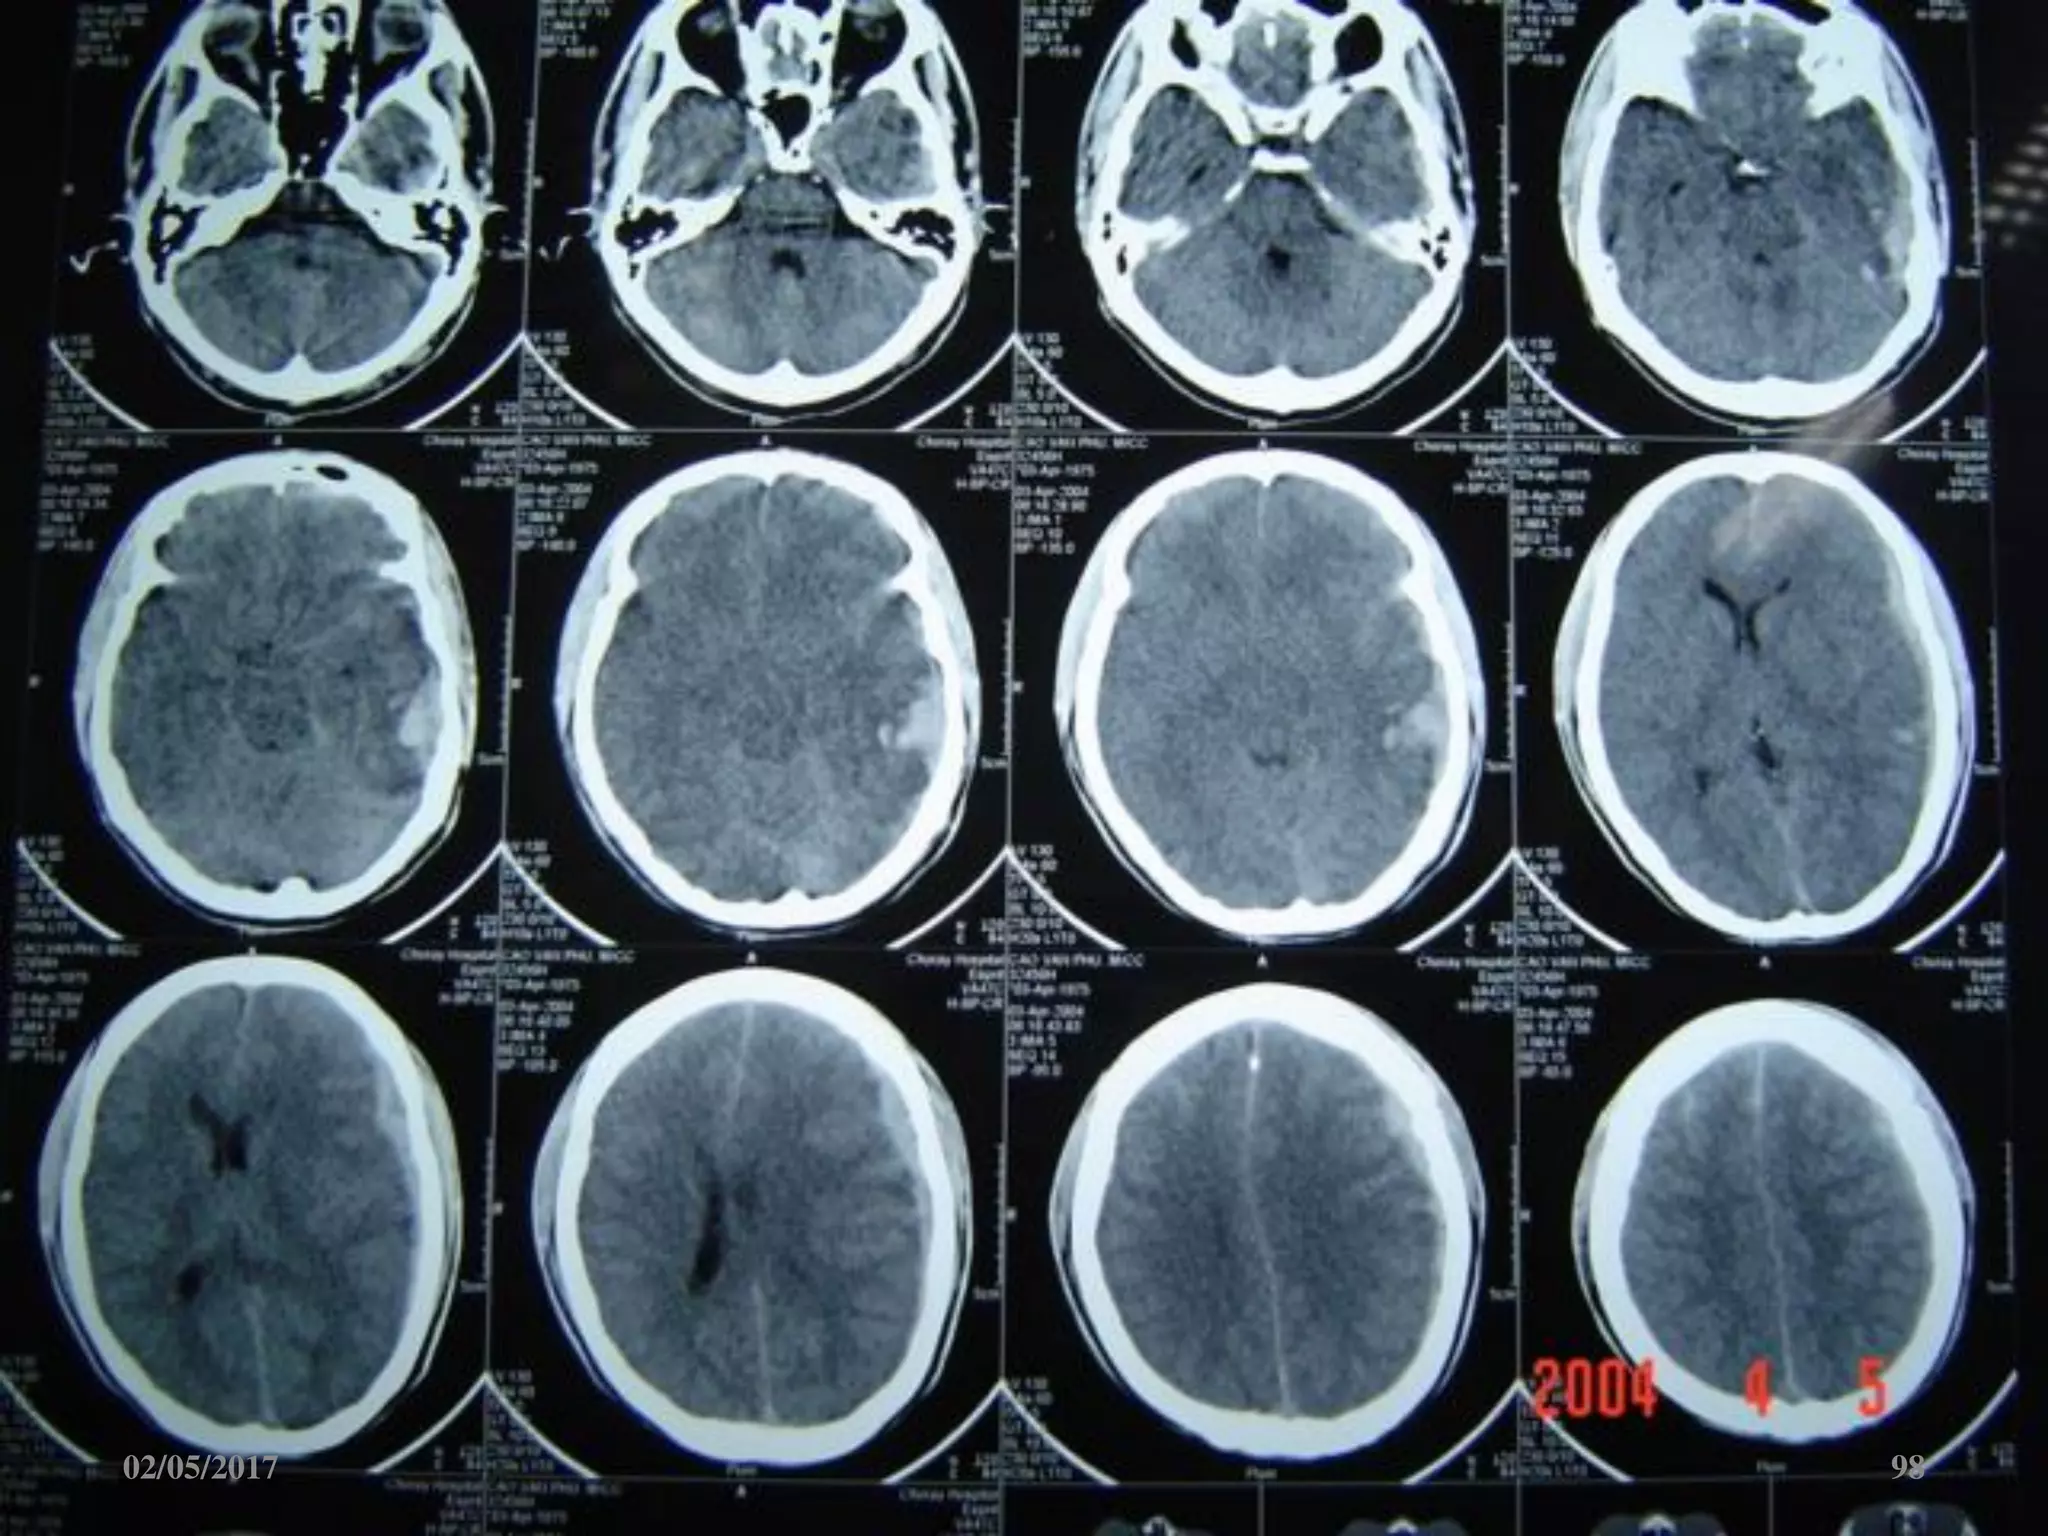

Dập não

• Vị trí: hay gặp ở trán

và thái dương.

• Cùng bên hoặc đối

bên với vị trí tác động

trực tiếp.

• Hình ảnh giảm đậm

độ do phù khu trú lẫn

tăng đậm độ do xuất

huyết rãi rác

02/05/2017 66

Phù não

• Giảm đậm độ lan tỏa.

• Mất ranh giới chất

trắng-xám.

• Xóa các rãnh não-bể

não.

• Não thất 2 bên nhỏ.